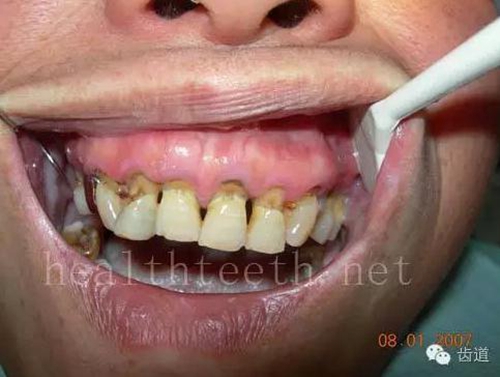

18歲全口牙牙根部的早期齲